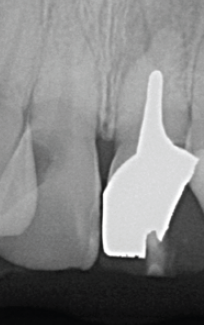

「慢性根尖性歯周組織炎に対して再治療を行なった症例」28歳 女性

術前のレントゲン像とCBCT像(図11・12)元々根尖部が吸収し大きな根尖病変を有する症例。

CBCTでは唇側皮質骨が広範囲に渡って吸収している。歯根が短く歯冠:歯根比が悪い状態。

外科的歯内療法のアプローチも考えられるが、歯冠:歯根比を考慮し非外科的歯内療法のアプローチを選択。根尖部のゲージングは#100を示した。作業長1ミリアンダーに抵抗形態を付与し、根管充填材が根尖外に漏出することを避ける。MTAセメント(PRO ROOT ®️)にて根管充填を行う(図13)。

術後5年経過、根尖周囲の透過像も軽減し、CBCT像では喪失していた唇側の皮質骨の再生が認められる(図14・15)。

(図11)右上1番は歯髄描壊疸

左上1番大きな骨欠損を伴う慢性根尖性歯周組織炎を呈する

(図12)左上1番の根尖部付近の骨はCBCT上で

唇側皮質根も含め大きく欠損していることが確認できる

(図13)右上1番は根尖開口部をMTAシーラーと

ウォームガッタパーチャにて封鎖に務める左上1番は抵抗形態を付与し

MTA製剤が極力根尖外に漏出しないように注意しながら充填を行なった

<術後5年後のレントゲン像とCBCT像>

左上1番の根尖周囲の歯周組織も再生が認められ、

右上1番の根尖部歯周組織も安定している

(図14)

(図15)